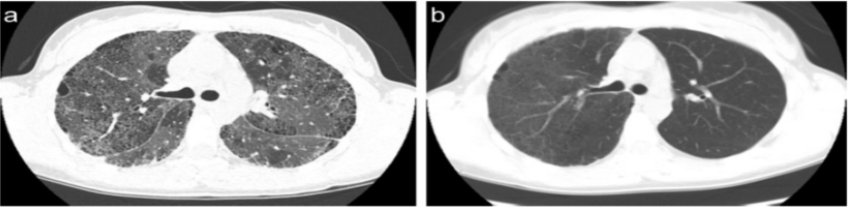

下图是ILD患者单侧肺移植术后3个月的随访胸部CT,可见右肺结构相对正常,但左侧肺的纤维化明显加重。

图片

图源:Respirology, 2016, 21(7):1173-1184.

下图是ILD双肺移植患者胸部CT,可见患者两肺结构相对正常,肺功能得到良好的保障。